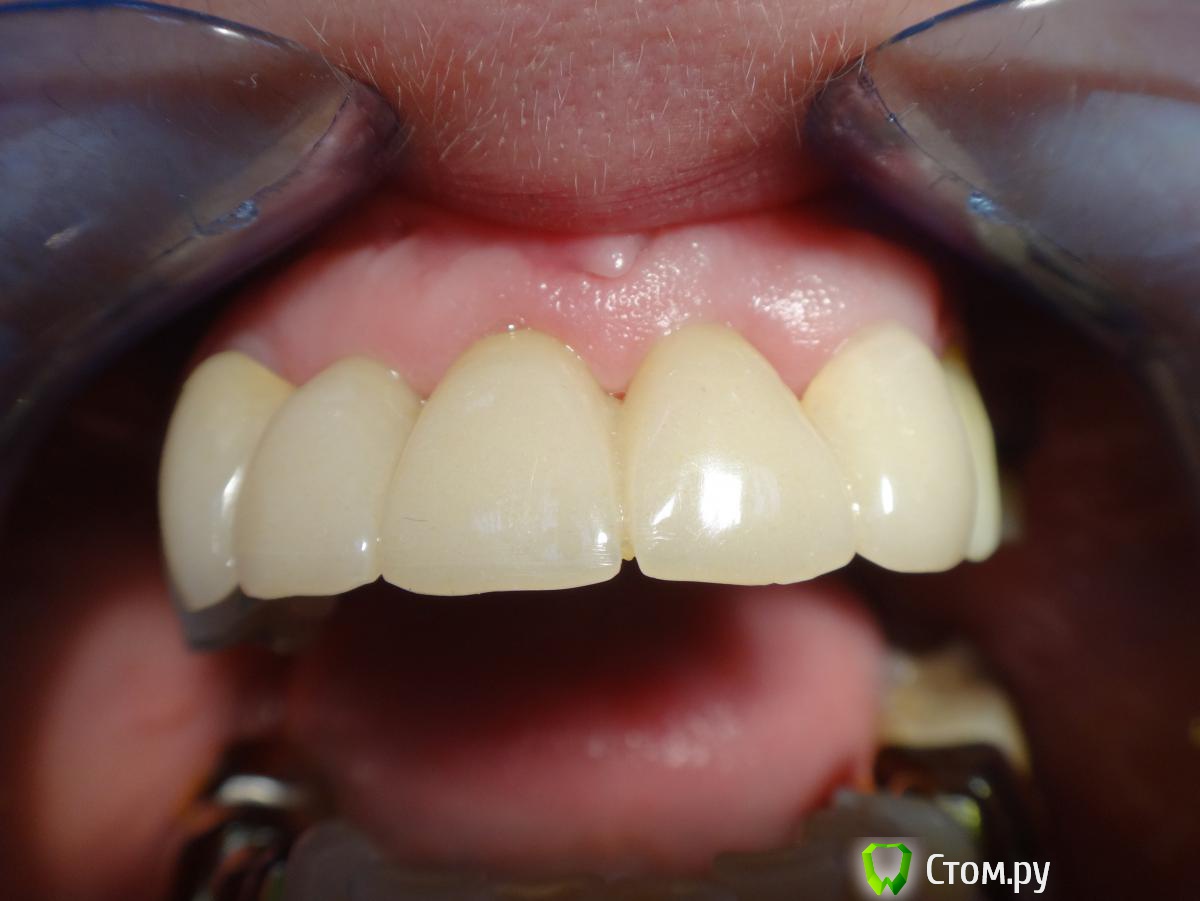

Kalipso Опубликовано 28 августа, 2014 Поделиться Опубликовано 28 августа, 2014 Я ставлю сразу после удаления .1 . Снимаю слепок до удаления , и прошу техника либо сделать коронку или wax up после чего по ключу сама изготавливаю .2. Удаляю .3.Жидкотекучим креплю коронку . Как- то так . Это наверно самая моя первая такая работа .http://s017.radikal.ru/i432/1408/7c/d61e22c1c7ae.jpg http://s018.radikal.ru/i519/1408/d2/23c0aebcd1b4.jpg http://s016.radikal.ru/i336/1408/51/3ede7c77a5d0.jpg http://s41.radikal.ru/i091/1408/cc/604419754cb7.jpg 3 Ссылка на комментарий

Kalipso Опубликовано 5 сентября, 2014 Поделиться Опубликовано 5 сентября, 2014 Мне кажется или зениты у двоек будут разной высоты? Что делать если после удаления десна выше зенитов соседних? Получается если поставить времянку сразу же и ограничить десну , то овоид получится выше чем надо. Если подождать после удаления несколько дней, опустится ли десна?Именно в этом случае в дальнейшем планировалось хир. удлинение .Если вы хотите сохранить овойд делайте временную конструкцию одномоментно с удаление , если найду покажу фото где пациент пришел на третий день после вид совершенно другой . Ссылка на комментарий

max9108 Опубликовано 5 сентября, 2014 Поделиться Опубликовано 5 сентября, 2014 Именно в этом случае в дальнейшем планировалось хир. удлинение .Если вы хотите сохранить овойд делайте временную конструкцию одномоментно с удаление , если найду покажу фото где пациент пришел на третий день после вид совершенно другой .Покажите. Буду благодарен. Я после удаления решил отложить овоид на 3 дня, так как после удаления край десны был выше зенитов соседних. Прикинул, что с натяжения хоть опустится немного ))) фантастика, да? или я все норм прикинул?)) За 3 дня ничего критического не произойдет, если попытаюсь сформировать овоид( сделать его чуть шире) ?пс. опыта пока маловато, так что заранее прошу простить Ссылка на комментарий

max9108 Опубликовано 14 сентября, 2014 Поделиться Опубликовано 14 сентября, 2014 Sluggy спасибо за фото. Тоже думаю, что через 2-3 дня лучше,чем сразу после удаления. Ссылка на комментарий

Slaggy Опубликовано 15 сентября, 2014 Поделиться Опубликовано 15 сентября, 2014 тут прикус будете поднимать?просто по фото 13 в контакте с антагонистом или мне кажется? Есть ответ про 13 Прошел месяц: Ссылка на комментарий